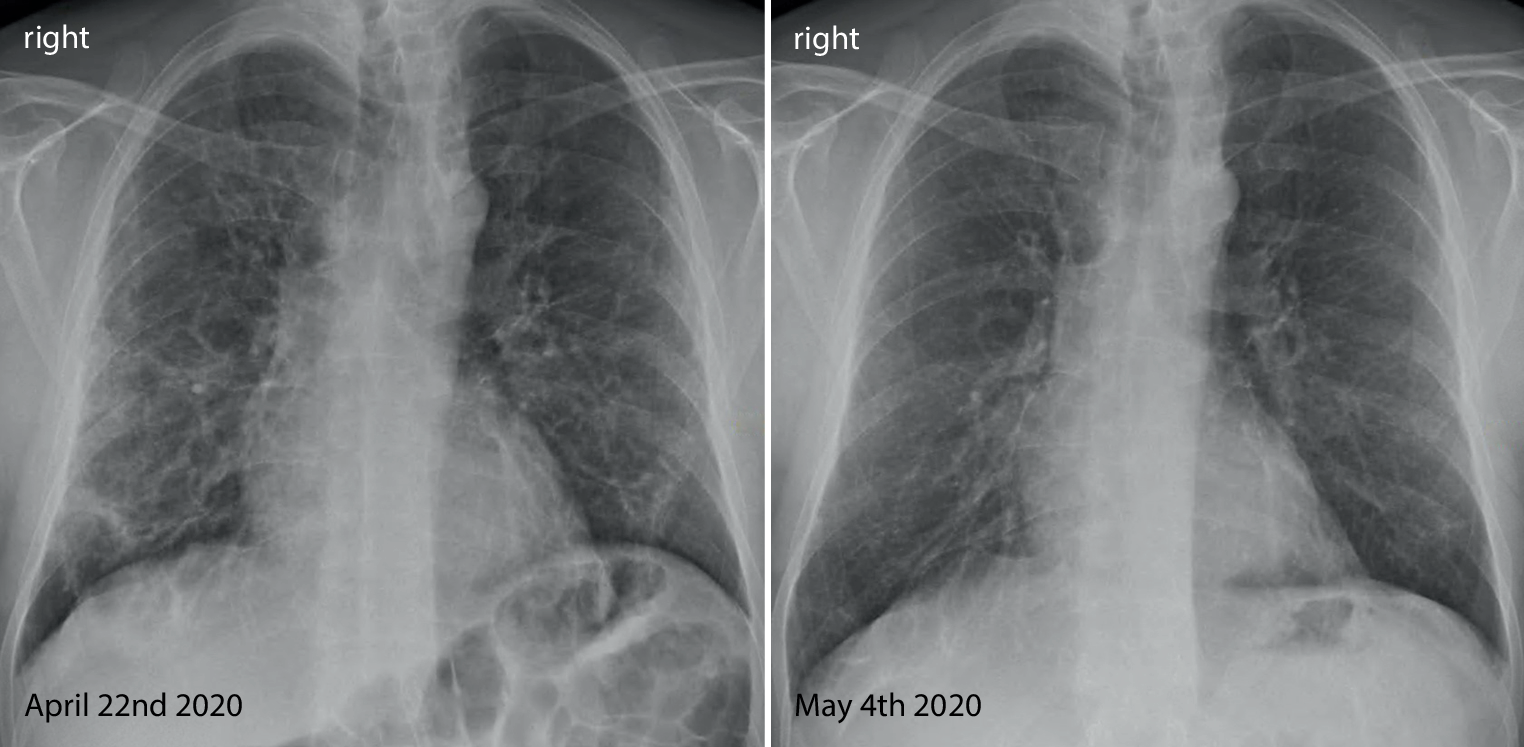

Fig. 3

Lung CT scan in the lower lobes showing ground glass, arcade-like bands of parenchymal consolidation, peribronchial consolidation and mild bronchiolectasis

His fever disappeared but he remained substantially short of breath during minor exertion. Suspecting Covid19 he saw a pulmonologist on 15 April. Physical findings were unremarkable and the chest X‑ray showed interstitial opacities with subpleural reticular densities predominantly in the lower fields (Fig. 1). On 20 April the computed tomography (CT) scan showed subpleural patchy ground glass opacities predominantly in the upper lobes (Fig. 2). The lower lobes in addition to ground glass showed arcade-like bands of parenchymal consolidation, peribronchial consolidation and mild bronchiolectasis (Fig. 3). The CT pattern was suggestive of organizing pneumonia. He was referred to the pneumology department for further diagnostic work-up.